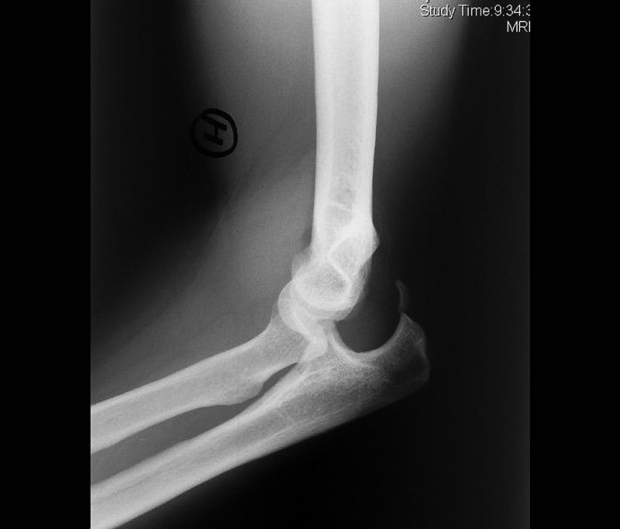

Secuelas de luxación de codo mal tratada. Deformidad en varo.

El paciente presenta impotencia funcional para mover el codo, dolor intenso, deformidad de la articulación (el brazo puede estar desplazado hacia fuera y hacia atrás o en otra dirección, según el patrón de luxación), hinchazón y, en ocasiones, puede existir compromiso arterial o neurológico.

La exploración objetiva la deformidad y el aspecto de acortamiento del brazo y desaparición de las referencias anatómicas del codo: triángulo de Nelaton.